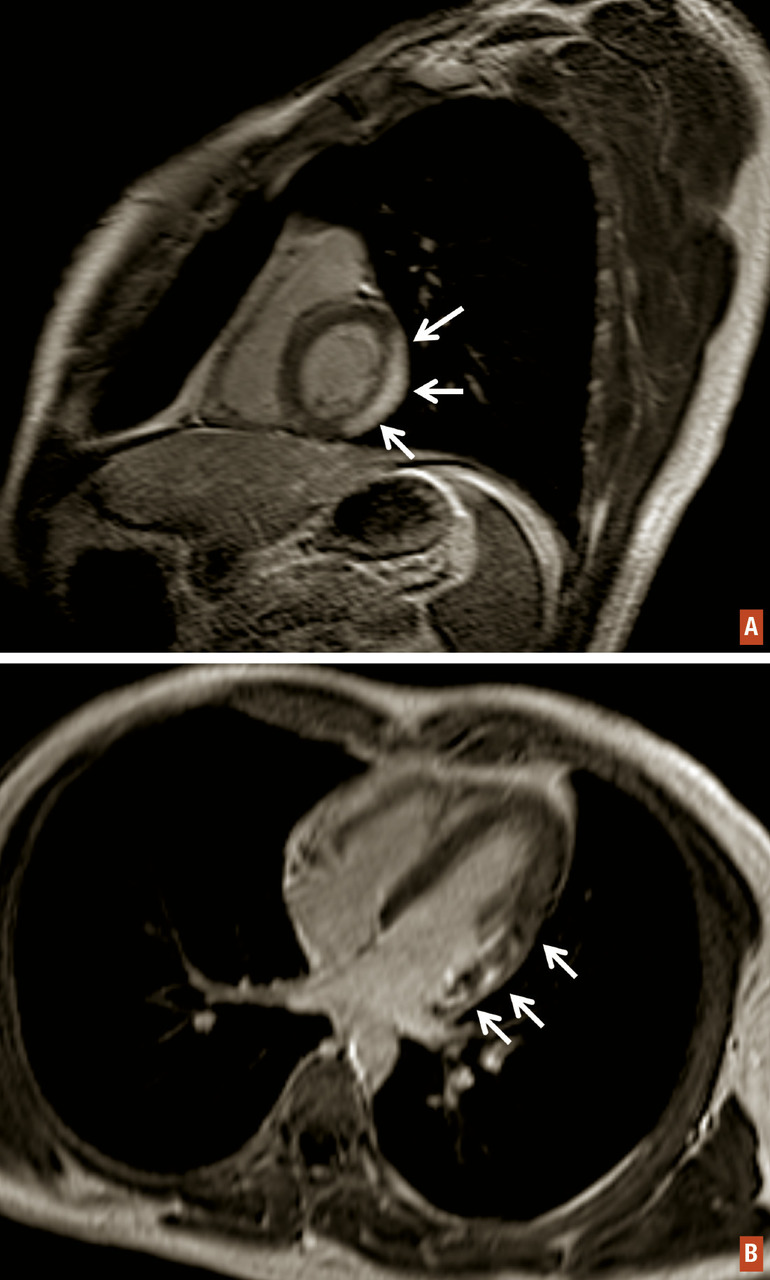

IRM cardiaque

Inutile en cas de péricardite aiguë virale bénigne, elle peut s’avérer utile en cas d’élévation concomitante de la troponine ou en cas de doute sur un syndrome coronaire aigu sans anomalie notable sur la coronarographie. Dans ces conditions, l’IRM est l’examen le plus sensible pour éliminer un infarctus sous-endocardique. Dans le cas d’une myopéricardite, les séquences de rehaussement tardif peuvent révéler des hypersignaux intramyocardiques ou sous-épicardiques (v. Formes cliniques).

Myopéricardite

Il s’agit d’une péricardite aiguë virale bénigne à laquelle s’associe une atteinte myocardique. Elle représente environ 30 % des cas. Le diagnostic repose le plus souvent sur l’élévation concomitante de la troponine sur le bilan biologique. Selon les descriptions de la douleur et l’aspect ECG, le diagnostic différentiel avec un infarctus du myocarde peut être délicate. L’IRM cardiaque est alors l’examen clé pour éliminer formellement l’hypo­thèse de l’infarctus sur les séquences de rehaussement tardif. En cas d’infarctus, il y a un hypersignal sous-endocardique systématisé. En cas de myopéricardite, l’hypersignal est intramyocardique ou sous-épicardique, nodulaire et non systématisé, parfois associé à un décollement péricardique (fig. 2) ; l’anomalie n’est toutefois présente que dans 30 % des cas, et l’IRM normale n’élimine donc pas le diagnostic de myopéricardite. Si la douleur est au premier plan, la prise en charge est identique à celle de la péricardite ; en absence de douleur, le traitement est débattu et non systématique.